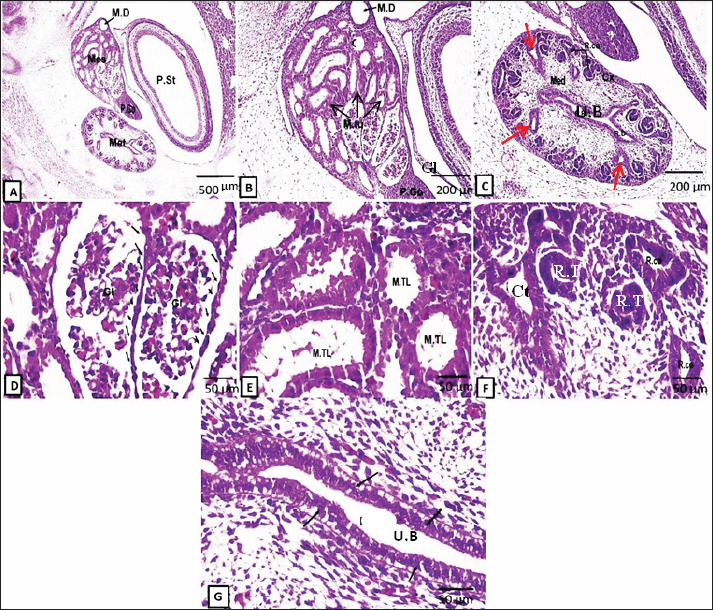

On the 15th day of gestation, both large, well-developed mesonephroi and undifferentiated metanephros appeared (Fig. 2a–g). At this stage, the mesonephric glomerulus is surrounded by a capsule lined by low-cuboidal epithelium. The cuboidal epithelium lined the mesonephric tubules, and some of the cells began to deteriorate. (Fig. 2d,e). The primitive metanephros consisted of the outer metanephrogenic mass derived from the intermediate mesoderm. The branched ureteric bud (future renal pelvis) was encircled by this mass. In addition to the formation of the renal cortex, the metanephrogenic mass initiates the formation of many solid and canalized renal tubules or future nephrons. The ureteric bud occupying the medulla was lined with simple columnar epithelium and received the collecting tubules (Fig. 2c,g).

Fig. 2. Representative photomicrographs of H&E-stained sections at the D15 of embryonic life (A.G): (A) (Scale bar 500 μm, ×~4): mesonephros (Mes) and metanephros (Met) together at abdominal cavity, mesonephric duct (M.D), primitive gonad (P.Go), and primitive stomach (P.St). (B) (Scale bar 200 μm, ×~10): higher magnification of primitive mesonephros containing glomeruli (Gl), mesonephric tubules (M.tu), mesonephric duct (M.D), and primitive gonad (P.Go). (C) (Scale bar 200 μm, ×~10): showing higher magnification of primitive metanephros as outer cortex (Cx), inner medulla (Med), renal corpuscles (R.Co), renal duct (R.D), collecting tubules (red arrows), and ureteric bud (UB). (D) (Scale bar 50 μm, ×~40): higher magnification of mesonephros glomeruli (Gl) surrounded by capsule lined by low cuboidal epithelium (black arrows). (E) (Scale bar 50 μm, ×~40): higher magnification of mesonephric tubules (M.Tl) lined by a single layer of low cuboidal epithelium. (F) (Scale bar 50 μm, ×~40): higher magnifications of renal corpuscles (R.co), renal tubules (R.T), and collecting tubules (Ct). (G) (Scale bar 50 μm, X40): higher magnification of the ureteric bud (U.B) (primitive renal pelvis) lined by the S. columnar epithelium.